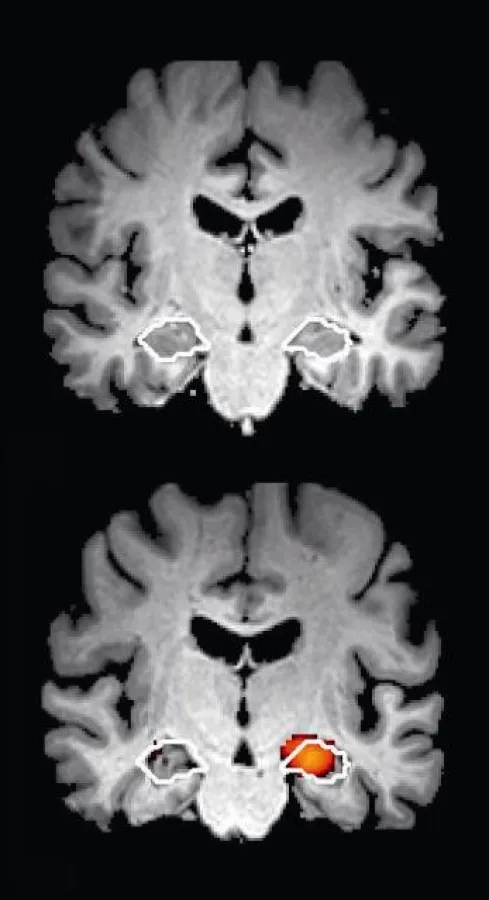

ARDX ist ein Verfahren, das den Einsatz etablierter, kognitiver Kurztests mit der modernen medizinischen Bildgebung und innovativen computergestützten Analyseverfahren kombiniert, und damit eine durch die Alzheimer-Erkrankung bedingte demenzielle Entwicklung mit großer Sicherheit ausschließen kann. Die ARDX ist eine den Patienten maximal schonende Untersuchung, da keine invasiven Eingriffe notwendig sind und durch die Magnetresonanztomographie-Untersuchung (MRT) keine schädigende Strahlung verabreicht wird.